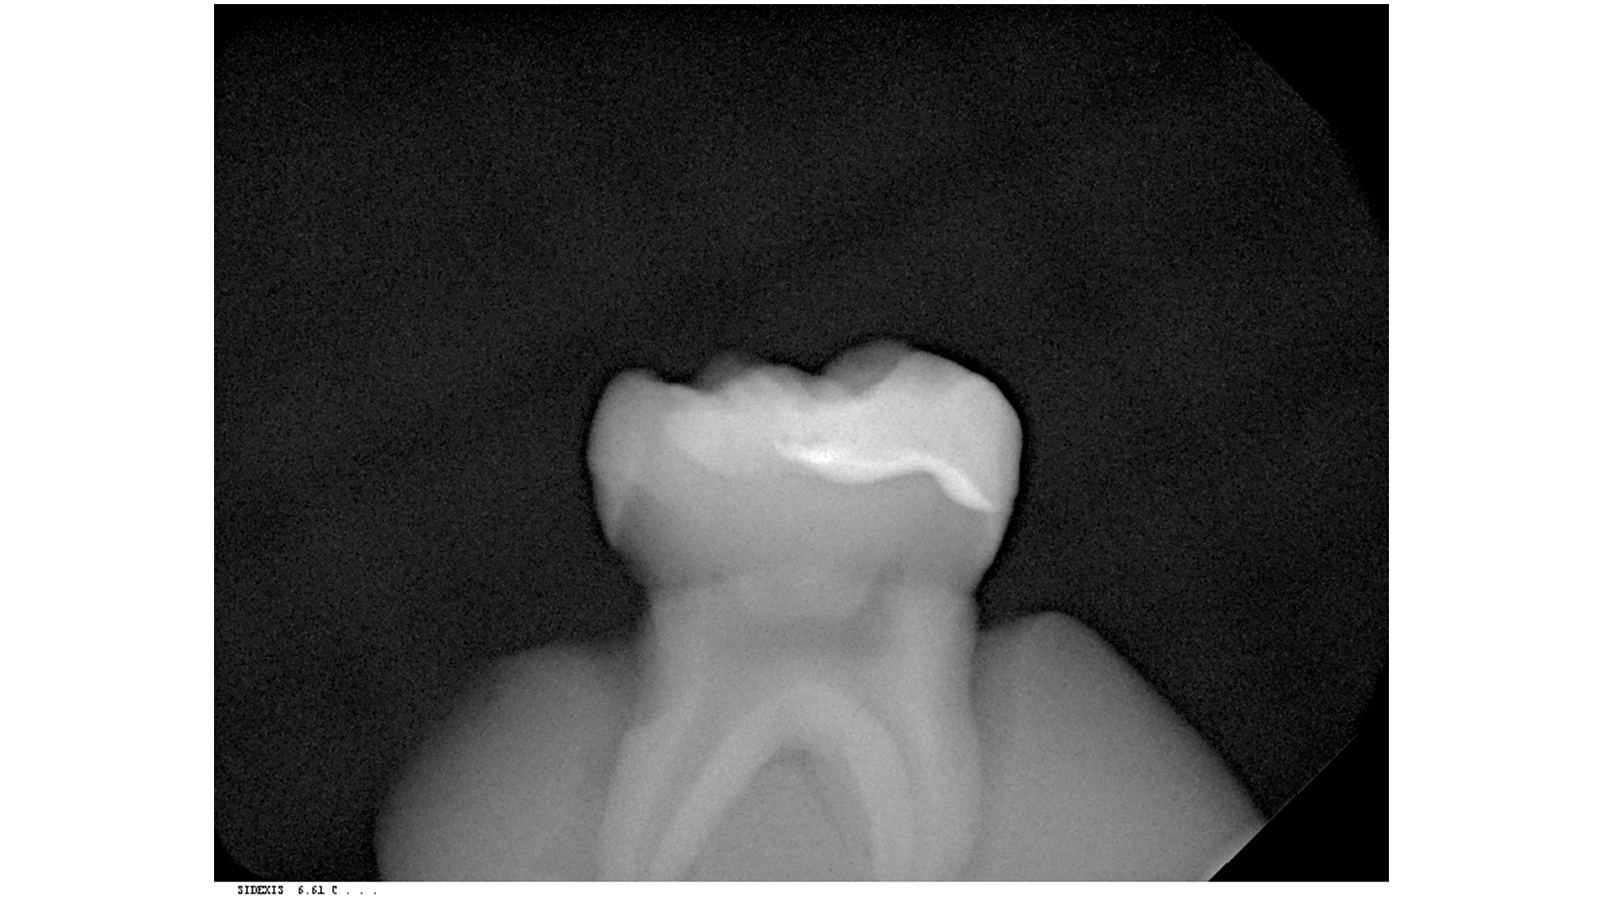

The composite filling is easily distinguished from the residual tooth structure due to its excellent radiopaque properties.

Charisma Opal Flow ensures an optimal, reliable diagnosis.